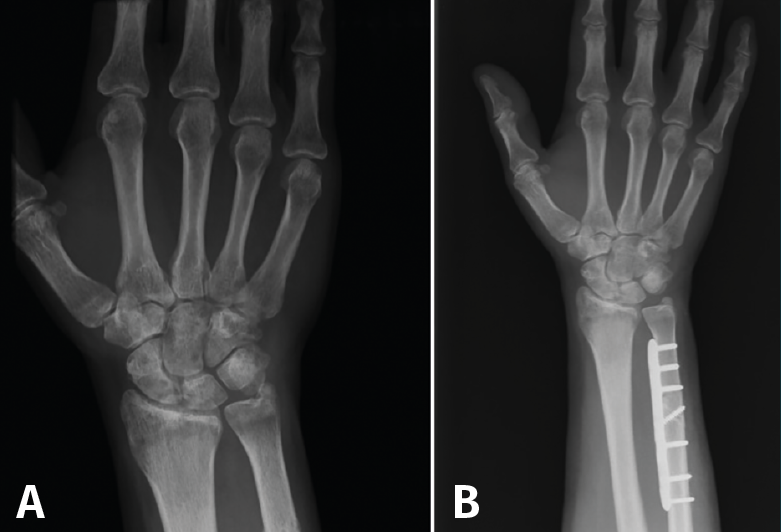

Típicamente, la osteotomía suele ser transversal u oblicua, y la osteosíntesis se lleva a cabo con una placa de compresión (Figura 4). Se realiza una incisión a lo largo del borde subcutáneo del cúbito. La longitud de la incisión está determinada por la longitud de la placa. La disección se lleva a cabo entre el ECU y el flexor carpi ulnaris (FCU). El periostio se incide longitudinalmente y se separa circunferencialmente. La placa debe proporcionar estabilidad y compresión con 3 tornillos bicorticales proximales y distales a la osteotomía. Algunas placas también permiten colocar un tornillo a compresión a través de la osteotomía cuando es oblicua.

Figura 4. A: muñeca con varianza cubital positiva; B: varianza corregida tras osteotomía de acortamiento cubital.